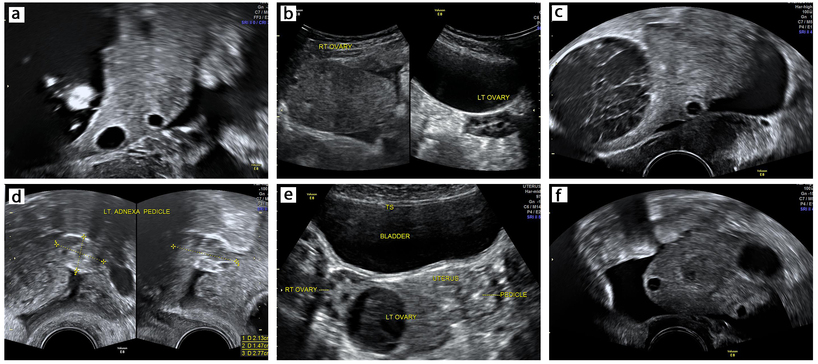

The ultrasound findings of adnexal torsion are summarized in Table 2 and depicted in Figures 1 and 2. An enlarged ovary, hemorrhagic cysts, abnormal position, free fluid and tenderness are commonly seen. The specific findings which can be used in diagnosis are: ovarian stromal edema, whirlpool sign of the twisted pedicle, absent Doppler flow and the follicular ring sign. The contralateral non-torsed ovary provides a convenient control to elicit the sonographic findings.

1

Non-specific ultrasound findings of ovarian torsion: (a) enlarged ovary secondary to a dermoid cyst; (b) enlarged right ovary as a result of torsion-induced edema with normal left ovary; (c) hemorrhagic cyst; (d) extraovarian pedicle; (e) torsed left ovary displaced to the right side; (f) free fluid.